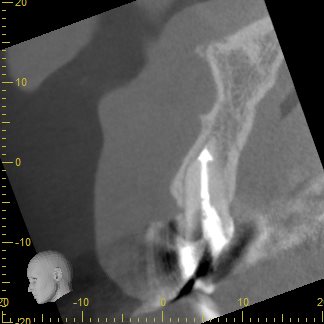

上の前歯のCT画像です。歯根の先の黒くなっている部分が感染し歯根周囲の骨が吸収しています。

まずは根管治療を行い、根管内の細菌を可及的に取り除き、根管充填を行います。

根管充填を行いしばらく経過観察を行いましたが、歯根の先の骨の回復が見られないため、その部分を切除する歯根端切除を行うこととしました。

切除後1年ほど経過したあとのCT画像です。

以前に見られた歯根の先の黒くなっている部分は消失し、歯根周囲に骨が回復してきていることが認められました😊